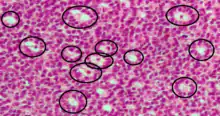

Los cuerpos de Call–Exner, con un aspecto parecido al del folículo, es una pequeña perforación entre las células de la granulosa relleno de un fluido eosinofílico.[1] Las células de la granulosa están generalmente organizadas aleatoriamente alrededor del espacio.

Son patognomónicos de tumores de células de la granulosa.

Histológicamente, estos tumores constan de islas monótonas de células de la granulosa con núcleos en "grano de café". Este aspecto de surco nuclear aparece también en el tumor de Brenner, un tumor ovárico de origen epitelial-estromal que puede distinguirse por nidos de células epiteliales de transición (urotelio) con surcos nucleares longitudinales (núcleos en grano del café) en un estroma fibroso abundante. [2]

Están compuestos de secreciones de las células de la granulosa empaquetados en una membranas y tienen relaciones con la formación de líquido folicular los cuáles se observan estrechamente organizadas entre las células de la granulosa.